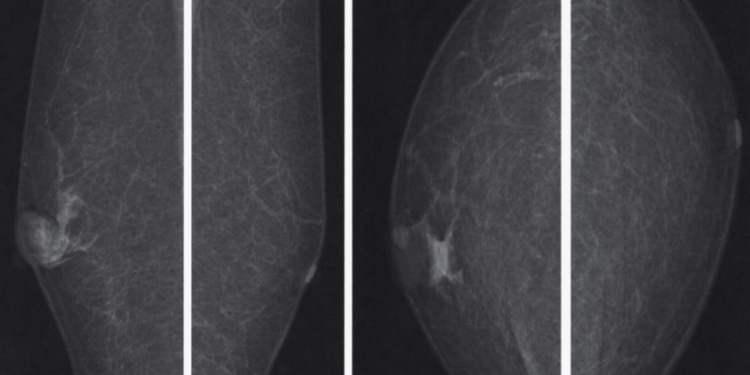

medicalplanet.su

В соцсетях уже гуляет хайповая версия: «ОСМС потеряло страх, мужчин отправляют на маммографию…» — звучит эффектно, но, как пояснил генеральный директор «Олимп» Ерлан Сулейменов, в этом нет никакого массового абсурда, сообщает SHYNDYK.KZ.

«Да, мужчины действительно проходят маммографию, и это не ошибка. Есть такой диагноз гинекомастия. Простым языком, в норме в грудной области должен быть жир, а не железа. Но, к несчастью, у некоторых мужчин тоже бывает железистая ткань. Если она появляется ― это уже тревожный сигнал», ― сказал он.

Сулейменов отметил, что маммография назначается мужчинам по строгим медицинским показаниям:

• при семейной истории рака молочной железы;

• при мутациях генов BRCA;

• при симптомах вроде уплотнения, асимметрии или выделений из соска.

«В ряде исследований маммография у мужчин из группы высокого риска выявляла рак чаще, чем у женщин со средним риском», — добавил он.

Гендиректор подчеркнул, что 619 мужчин за два года — это далеко не «медицинский беспредел». Это может быть нормальной статистикой, следствием реальных показаний или единичными случаями, требующими разбирательства.

«Нарушения, безусловно, бывают, но с этим нужно работать точечно. Медицина — это не «всё плохо» и не «всё хорошо». Лечить нужно не болезнь, а человека с болезнью», — подытожил Сулейменов.